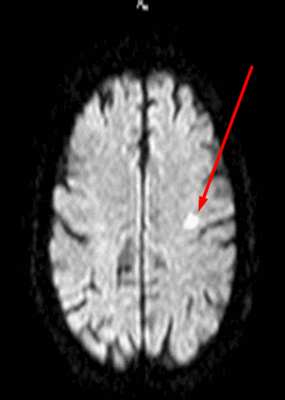

Нейровизуализационные методы: КТ, МРТ головного мозга, МР-ангиография (артерии и вены головного мозга ), при необходимости рентгеноконтрастная церебральная ангиография. Нейровизуализация позволяет исключить другие заболевания (опухоль, гидроцефалию) и подтвердить сосудистый характер нарушений. Предпочтительнее МРТ головного мозга, на которой выявляются характерные для хронической ишемии мозга изменения:

- лейкоареоз — изменение белого вещества вокруг желудочков головного мозга (на рисунке 1, белое свечение вокруг желудочков);

- лекоэнцефалопатия — поражение белого вещества головного мозга (на рисунке 1 и 3, светлые участки в подкорковом веществе);

- малые инфаркты, ишемические инсульты (рисунок 3);

- множественные микрокровоизлияния (рисунок 2 — темные участки);

- атрофия коры головного мозга.

Существует зависимость между типом и выраженностью морфологических изменений мозгового вещества и стадией заболевания [4] [6] .